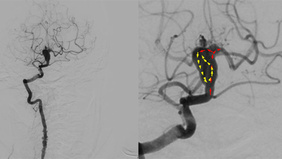

Tandem Stenosis & Extracranial Carotid Rescue Stenting

By Muralidharan VETRIVEL

Published on December 11, 2025